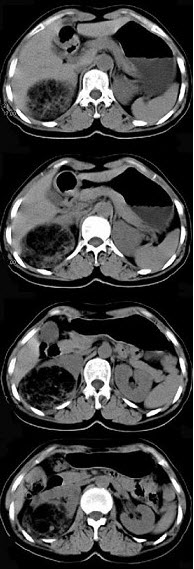

女,53岁,右侧轻度腰背酸痛,行CT检查,如图所示,可能的诊断为( )

A:右肾上腺髓样脂肪瘤

B:右肾上腺腺瘤

C:右肾上腺嗜铬细胞瘤

D:右腹膜后脂肪瘤

E:右肾血管平滑肌脂肪瘤